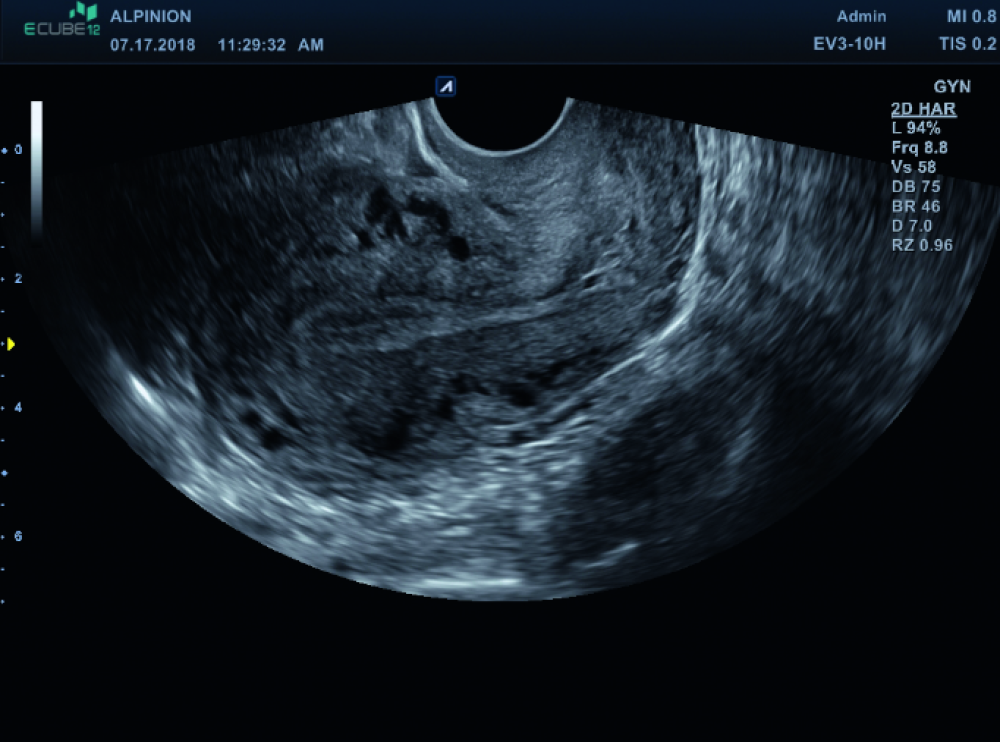

Moderne Frauenheilkunde stellt höchste Anforderungen an Bildqualität, Bedienkomfort und Vielseitigkeit. ALPINION unterstützt Gynäkologinnen und Gynäkologen mit leistungsstarker Ultraschalltechnologie, die sowohl im Praxisalltag als auch im klinischen Umfeld überzeugt. Unsere Systeme liefern hochauflösende Bilder bei transabdominaler und transvaginaler Sonografie – für eine sichere, schnelle und präzise Diagnostik in allen Phasen der Frauengesundheit.

• Kristallklare Bildgebung – auch bei feinsten Strukturen

• Speziell entwickelte Endokavitärschallköpfe für höchsten Patientinnenkomfort

• Erweiterte Doppler-Technologie zur Gefäßdarstellung und Beurteilung pathologischer Befunde